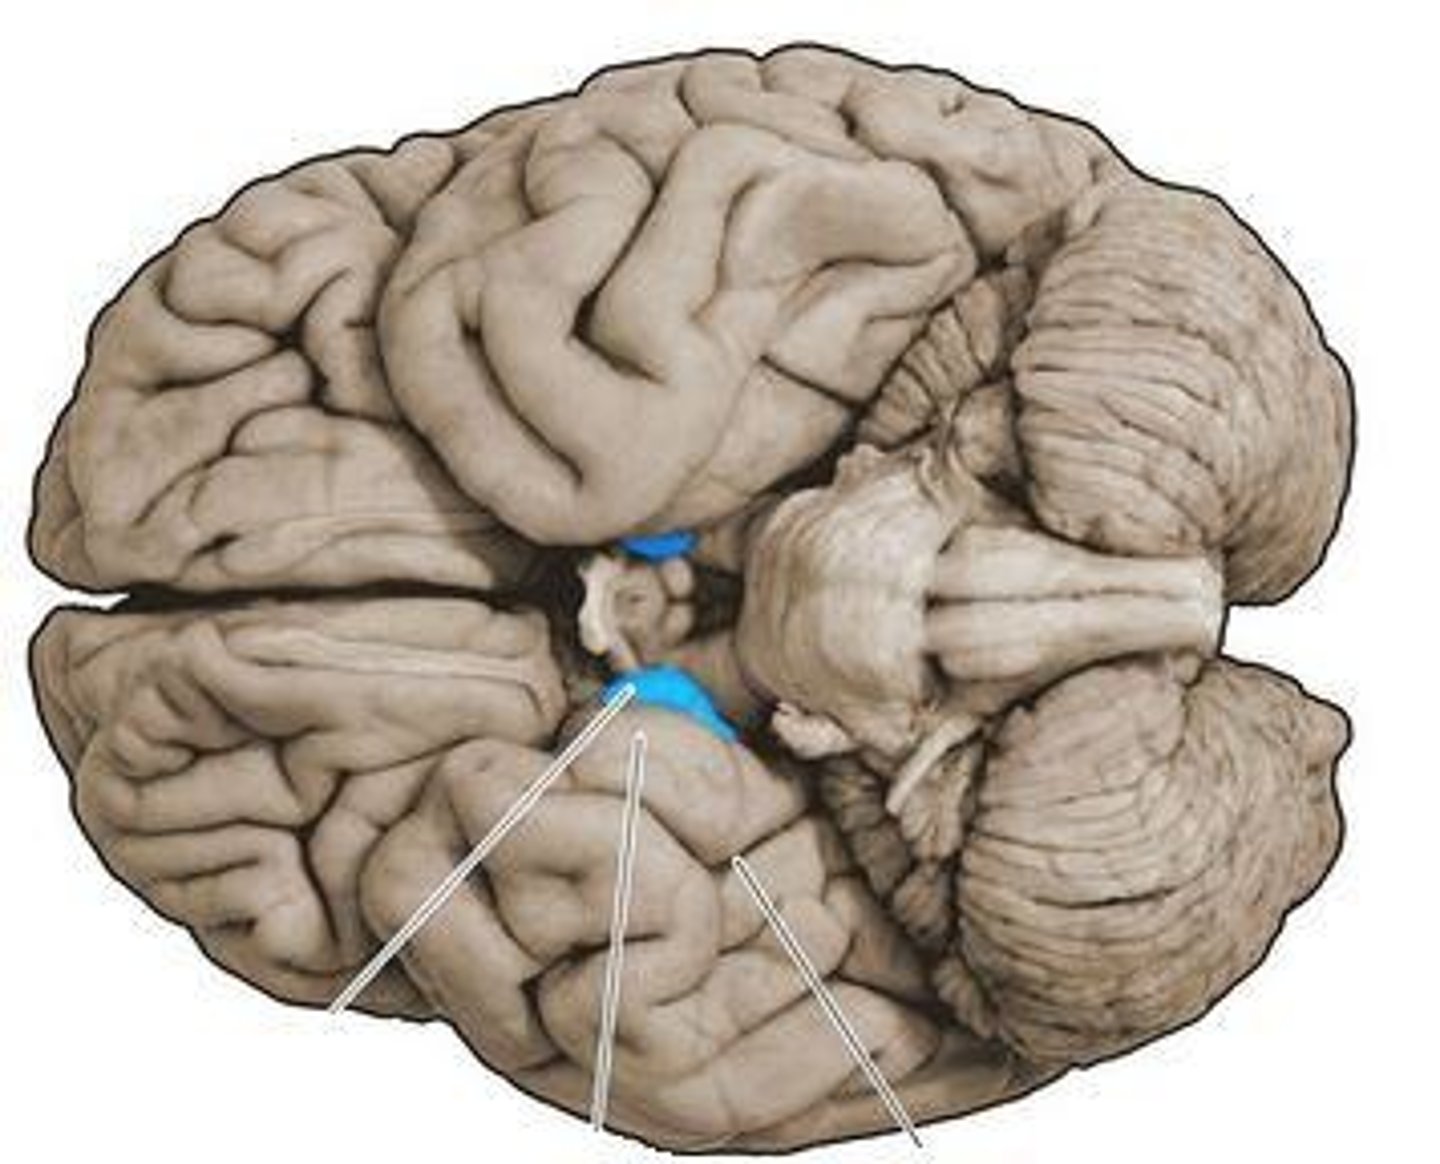

optic chiasm

point at which optic nerve fibers cross in the brain

optic tracts

the continuation of the optic nerve fibers beyond the optic chiasma

glossopharyngeal nerve (CN IX)

Mixed cranial nerve that transmits taste and touch sensations from posterior one-third of the tongue and innervates a pharynx muscle involved in swallowing; and increases secretions of the parotid salivary glands

vagus nerve (CN X)

Mixed cranial nerve that innervates structures in the head and neck and in the thoracic and abdominal cavities; major role in the control of cardiac, pulmonary, digestive, and urinary function ;also involved in swallowing, and speech

hypothalamus

a neural structure lying below the thalamus; directs eating, drinking, body temperature; helps govern the endocrine system via the pituitary gland, and is linked to emotion

pituitary gland

endocrine gland at the base of the brain